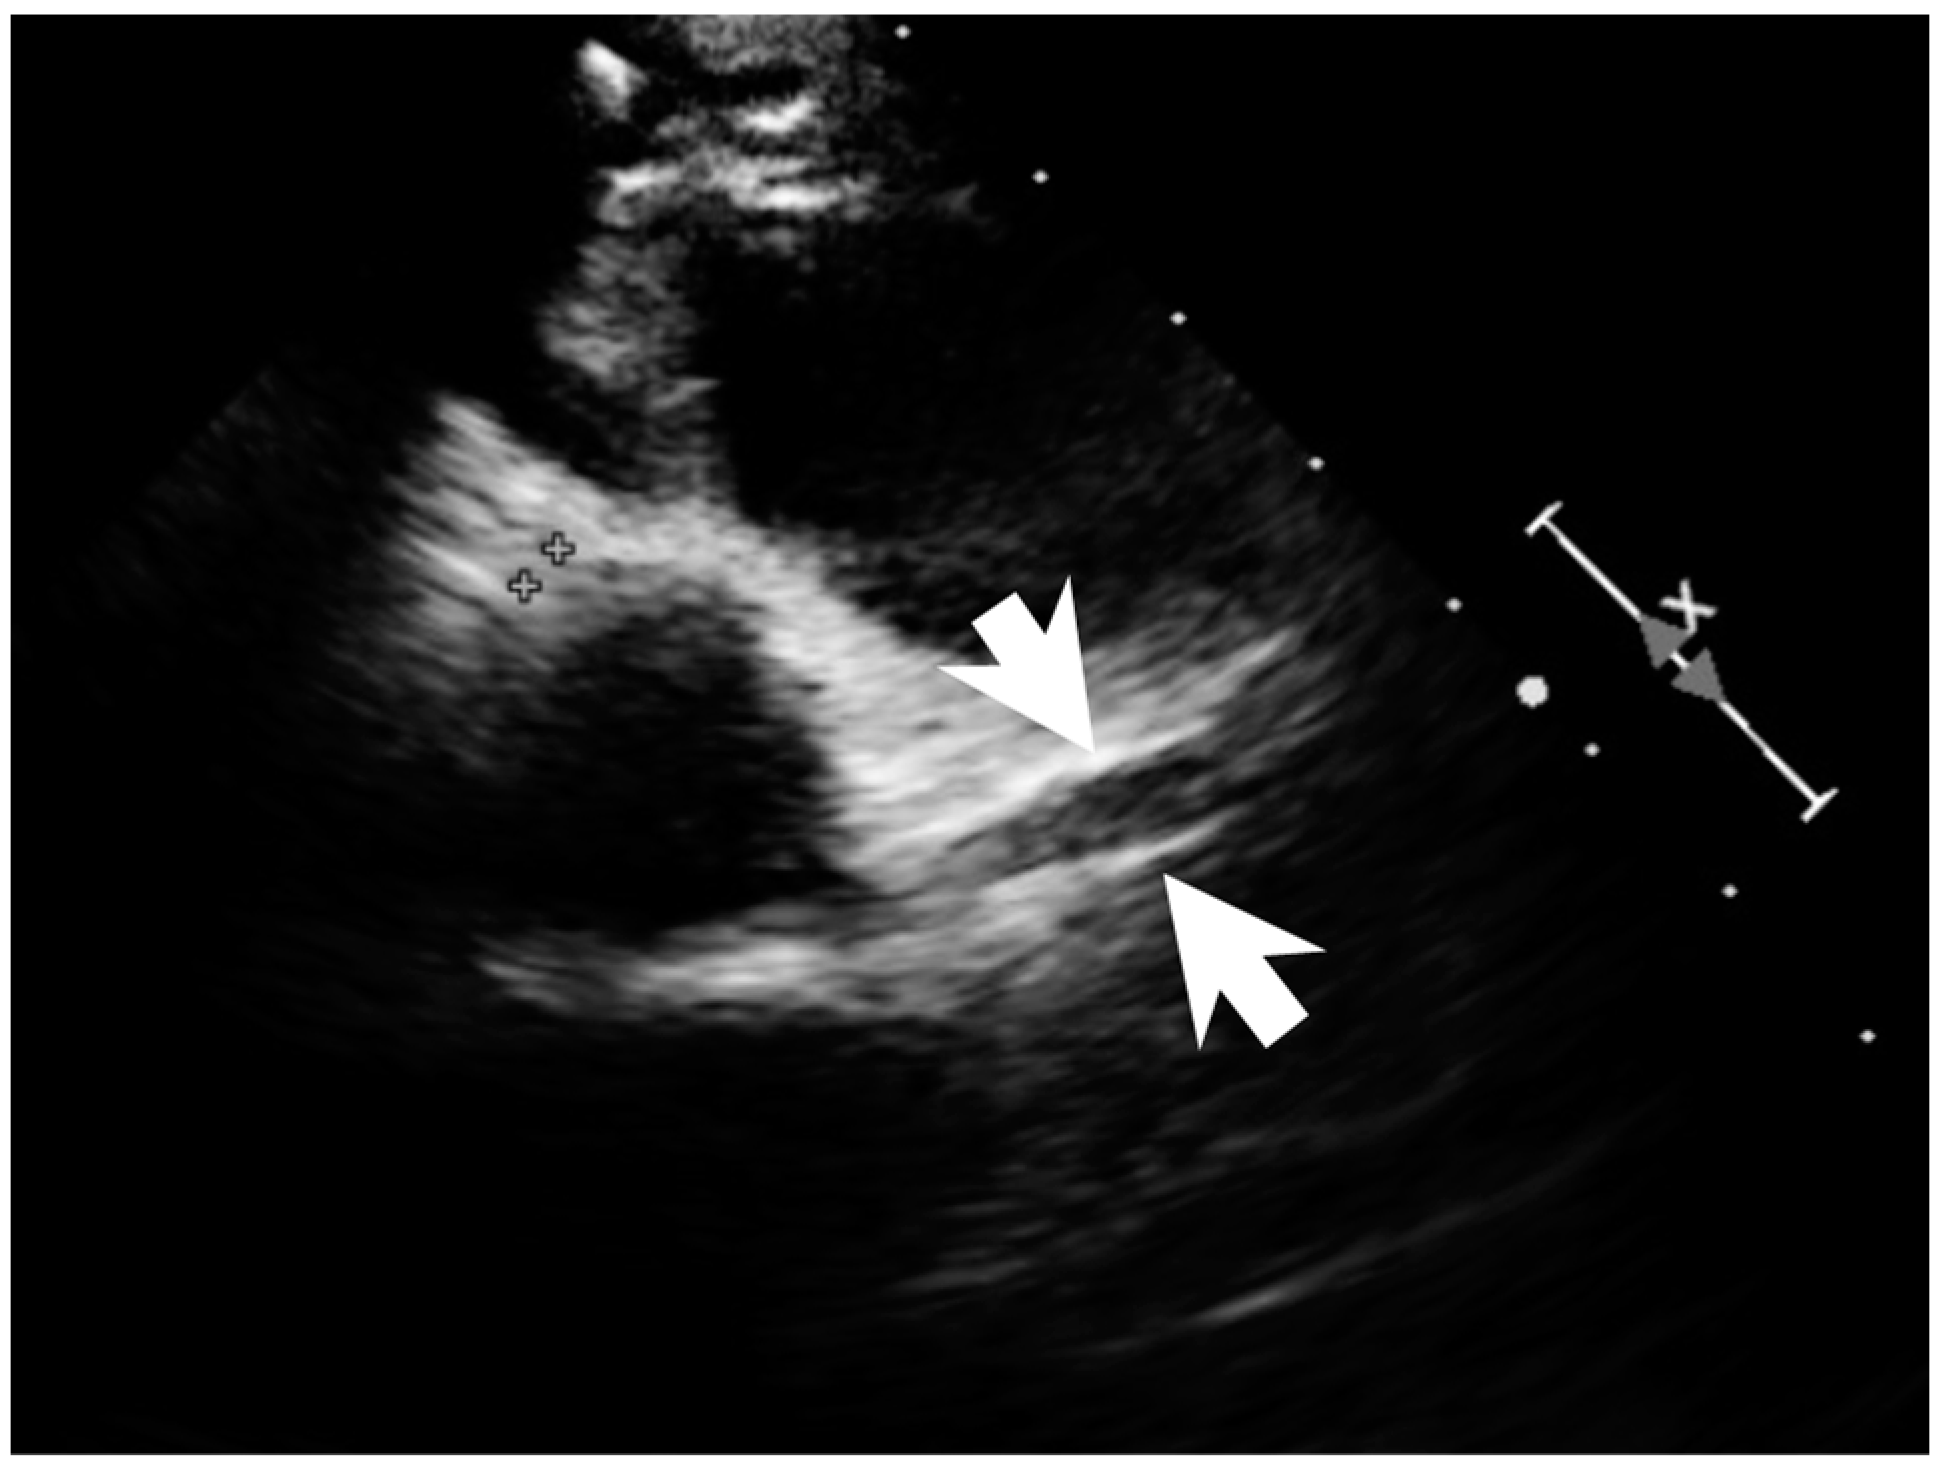

Figure 4.

Coronary dilatation of LCA on the echocardiography (arrows).

A previously healthy eight-year-old girl presented with fever for 1 day, accompanied by several days of vomiting and non-bloody, watery diarrhea. She also suffered from periumbilical abdominal pain for 5 days. The location of the pain shifted to the right lower quadrant 1 day before her arrival. She was brought to our outpatient department for suspicion of acute appendicitis. She had no cough, conjunctivitis, rhinorrhea, joint pain, or consciousness disturbance. A plain radiograph showed diffuse bowel ileus. The number of leukocytes in the blood was 19,800/μL with neutrophiles predominant (88%), and the level of C-reactive protein (CRP) was 30.67 mg/dL. In addition, prolonged INR (1.45) and APTT (38.7 s) and elevated D-dimer (7247.00 ng/mL) and erythrocyte sedimentation rate (ESR) (67 mm/h) were also noticed. Her platelet count was 337,000/μL. Her blood pressure was 115/74 mmHg, and her heart rate was 95 beats per minute. Acute appendicitis, leading to sepsis and disseminated intravascular coagulation, was initially suspected. Empirical antibiotics were prescribed along with intravenous fluid resuscitation. Computer tomography scan of the whole abdomen revealed borderline wall thickening of the appendix. She received a laparoscopic appendectomy on the second day of admission due to persistent abdominal pain with peritoneal signs. However, after the operation, she presented with hypotension, tachycardia, and oliguria. No signs of bleeding were observed. She was transferred to the intensive care unit. Broad-spectrum antibiotics and inotropic agents were administered. Three days after surgery, a bilateral bulbar non-exudative conjunctival injection developed. Swelling and erythematous change in digits were also noted (Figure 1). Echocardiography showed a decrease in systolic function with the use of dopamine and dobutamine, and the ejection fraction showed only 54.4%. Pericardial effusion and mitral regurgitation were also noticed. There was no coronary artery dilatation initially. Elevated troponin-I (0.91 ng/mL) was also found. Elevated white blood cell counts (20,500/μL), ESR (38 mm/h), and CRP (20.85 mg/dL) were notable in repeated blood tests. No other viral or bacterial pathogen was isolated. The diagnosis of Kawasaki disease shock syndrome was highly suspected. Therefore, we prescribed aspirin (4 mg/kg/day) and IVIG (1 g/kg/day). Her fever soon subsided. She was weaned from inotropic agents. She was transferred to the ordinary ward on the ninth day after admission. Pathologic reports of her appendix showed infiltration of acute inflammatory cells in the appendix (Figure 2), with no mucosal erosion–ulceration (Figure 3). The picture of the appendix was not compatible with the clinical finding of turbid ascites. A concomitant inflammatory source in another area was suspected. She was discharged on the thirteenth day. However, she developed a fever again 20 days after the onset of the disease. She also developed muscle pain and neck pain. The swelling and pain in her feet improved, but red eyes were again noted. Red lips and strawberry tongue were also observed. There were no skin rashes. Elevated white blood cell counts (10,600/μL), ESR (109 mm/h), CRP (13.58 mg/dL), and D-dimer (3133.00 ng/mL) levels were noted. A Group A streptococcus rapid test showed positive. She was admitted again and given an antibiotics treatment. Echocardiography was performed. Coronary dilatation of the left coronary artery (LCA) (0.48 cm; Z-score = 3.15) and right coronary artery (RCA) (0.252 cm; Z-score = 0.15) were found (Figure 4). Some maculopapular rashes developed on four limbs 3 days later, and fever persisted. Refractory KD was diagnosed. Immunoglobulin (2 g/kg/day), high-dose aspirin (47.2 mg/kg/day), and oral prednisolone (60 mg/day) were administered. Her fever subsided 2 days later after IVIG administration. We changed the aspirin to low dose (4 mg/kg/day) and kept it for 5 months. Skin rashes subsided 3 days later after IVIG use. Desquamations of the fingers were later found. Red eyes and lips also improved. Prednisolone gradually tapered after 6 weeks of treatment. After 3 months of follow-up, the coronary dilatation subsided. The child recovered completely and was regularly followed up in the outpatient department.

In children of KD presenting with appendicitis, 30% (4/13) have cardiac involvement with coronary dilation or aneurysms [7,13]. Children with KDSS seem to have a higher rate of coronary artery abnormalities than children with KD [8,9,10]. Furthermore, left ventricle dysfunction represented by reduced ejection fraction (<55%) were found to be more common in the KDSS group than in the hemodynamically stable KD group in children [6,14]. The more severe inflammatory process with increased cardiac involvement may lead to hemodynamic instability in children with KDSS.